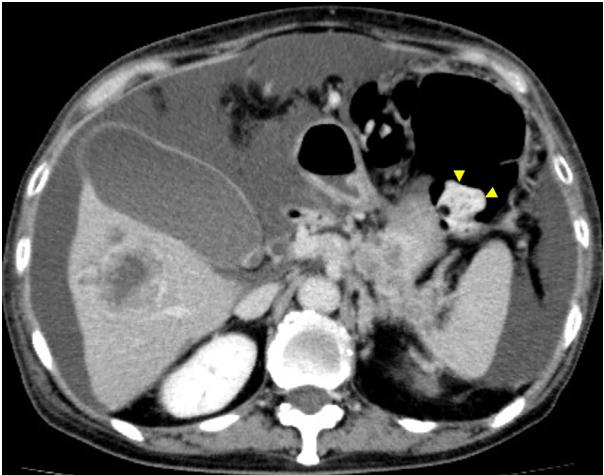

磁共振成像(MRI)显示舌内肌内1.5×2.3×2.0cm的肿瘤。肿瘤在T1加权像上呈低信号,在T2加权像上呈非均匀高信号(图2)。PET/CT发现舌肿瘤;胰腺体肿瘤从脾静脉侵犯到前面肾旁间隙;多发性肝肿瘤;肺肿瘤;盆腔内的腹膜肿块被认为是播散性的(图3A和B)。CT增强扫描显示胰体肿瘤广泛侵犯脾窦静脉至肾旁前间隙。附着在胰腺肿瘤上的胃浆膜层被破坏,肿瘤侵入胃壁(图4)。因为胃的大部分解剖形态保持不变(图4),所以被认为是胰腺癌侵犯胃,而不是胃癌侵犯胰腺。

图4对比增强CT。增强CT显示胰腺体肿瘤。附着在胰腺肿瘤上的胃浆膜层被破坏,肿瘤侵入胃壁(黄色箭头)。胃左动脉淋巴结肿大(红色星号)。然而,胃的浆膜层大部分保持形状。